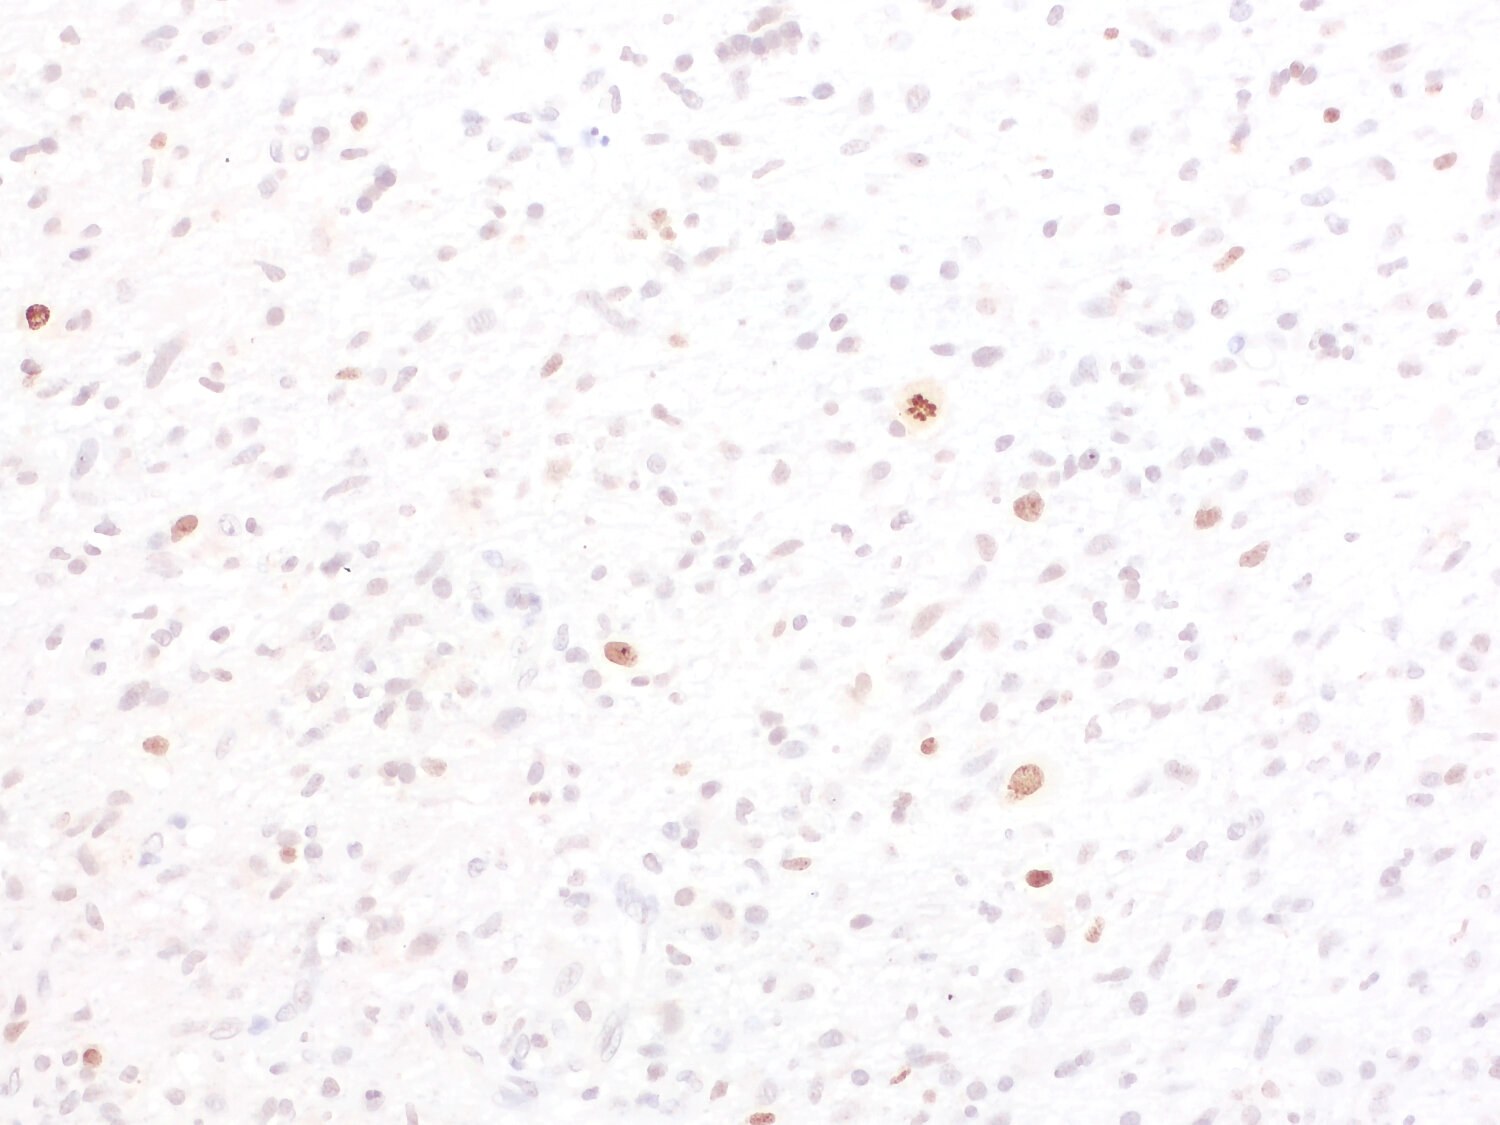

Detection of proliferation antigen Ki-67 in human colon cancer

Expression of the nuclear protein Ki 67 is strictly associated with cell proliferation and preferentially expressed during the late G1, S, G2 and M phases of the cell cycle. Resting cells (G0 phase) lack Ki 67 expression .

Immunohistochemical detection of Ki 67 is a simple and reproducible method to determine the tumour proliferative index and is a predictive and prognostic biomarker in certain types of human cancer, such as breast cancer, gastric cancer or prostate cancer. Moreover, higher Ki 67 scores may be associated with increased tumor sensitivity to radiation therapy and chemotherapy.

In preclinical and clinical studies Ki 67 expression is used as a pharmacodynamic biomarker. Absence of a decrease in Ki 67 early in treatment might be predictive of therapeutic failure.

IP: not tested yet ICC: not tested yet IHC: not tested yet IHC-P: 1 : 2000 gallery |